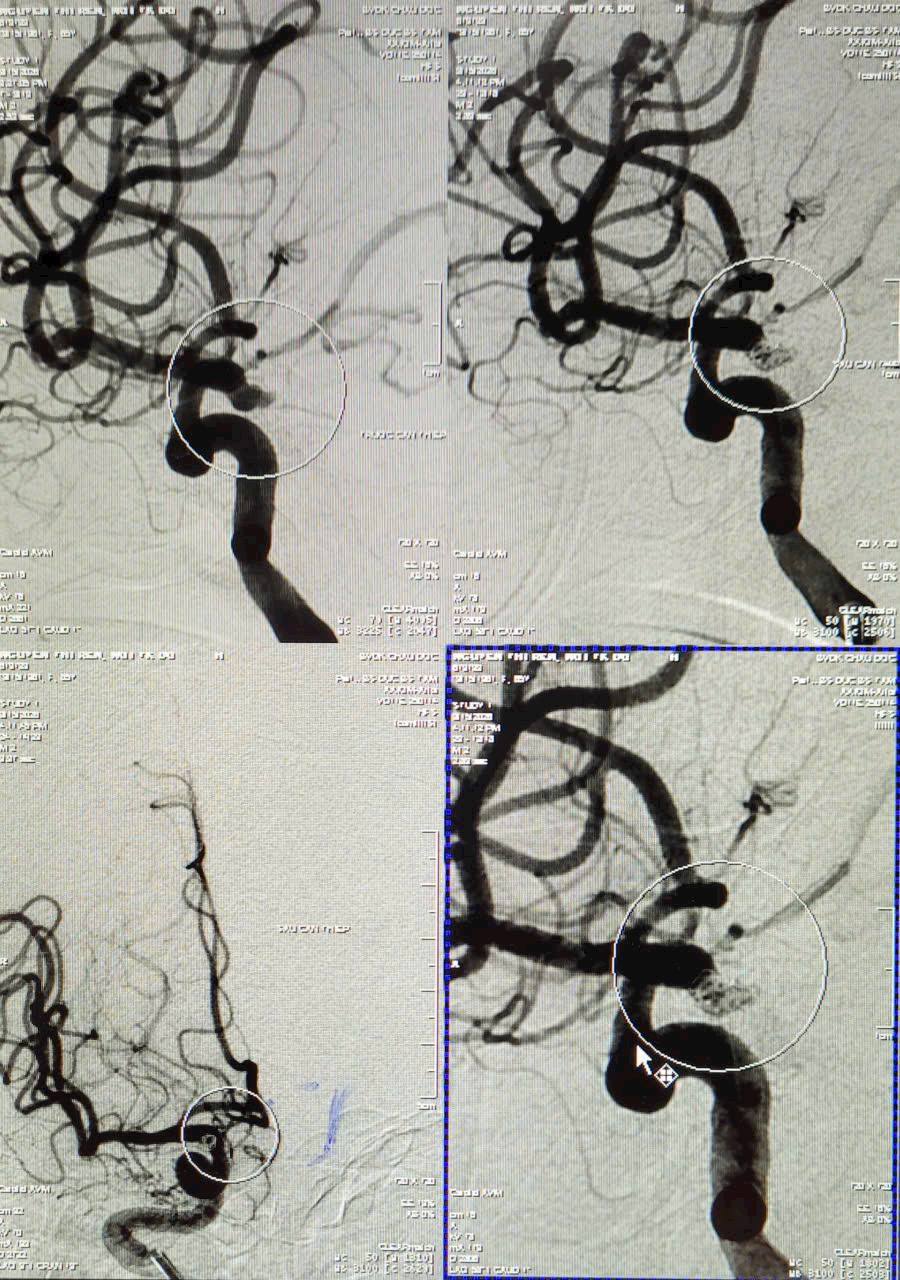

Các bác sĩ khoa Nội Thần kinh – Đột quỵ tại Bệnh viện Đa khoa Châu Đốc vừa can thiệp cấp cứu thành công một trường hợp vỡ túi phình mạch máu não gây xuất huyết dưới nhện – một tình trạng nguy hiểm có thể đe dọa tính mạng nếu không được xử trí kịp thời.

Bệnh nhân là bà Nguyễn Thị R., 65 tuổi, nhập viện trong tình trạng đau đầu dữ dội kèm nôn ói. Qua thăm khám và thực hiện các cận lâm sàng cần thiết, bác sĩ xác định bệnh nhân bị xuất huyết não khoang dưới nhện hai bán cầu (Hunt-Hess độ 3) do vỡ túi phình động mạch não, đồng thời có bệnh nền tăng huyết áp.

Đây là một kỹ thuật can thiệp nội mạch hiện đại, đang được áp dụng rộng rãi trên thế giới trong điều trị túi phình mạch não. Thay vì phải mổ mở hộp sọ, bác sĩ thực hiện thủ thuật bằng cách đưa một hệ thống dụng cụ rất nhỏ đi từ động mạch đùi, luồn theo hệ thống mạch máu lên đến vị trí túi phình trong não.

Tại vị trí túi phình bị vỡ, bác sĩ đưa vào những vòng kim loại nhỏ gọi là coil để lấp đầy túi phình. Khi được đặt đúng vị trí, các coil này sẽ làm ngưng dòng máu chảy vào túi phình, giúp ngăn chảy máu tiếp diễn và phòng ngừa vỡ lại, từ đó bảo vệ mô não xung quanh.

Nhờ sự phối hợp nhịp nhàng và xử trí kịp thời của ê-kíp can thiệp, ca bít coil đã được thực hiện thành công, giúp kiểm soát tình trạng xuất huyết và ổn định tình trạng của bệnh nhân.